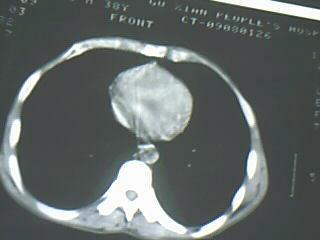

以下是引用随光逐影在2009-8-7 15:40:00的发言:[br]考虑右肺继发性肺结核并右肺上叶空洞形成,两肺支气管播散;不排除右肺上叶空洞内霉菌感染可能。

以下是引用jiangjing在2009-8-7 14:38:00的发言:[br]右上肺张力空洞,酐珞坏死灶,支气管扩张,多发播散灶,纵膈淋巴结显示,胸膜增厚---结核